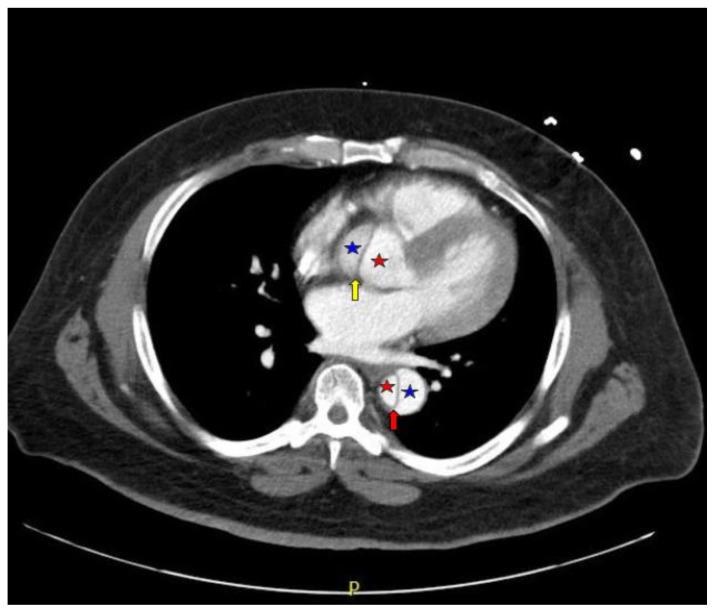

Acute aortic dissection is a life-threatening event caused by separation of the aortic layers that requires prompt management and surgical consultation. We present the case of a 53-year-old male who developed acute, severe chest pain radiating to his back at a community hospital and was transferred to a tertiary center for definitive surgical management. The patient's aortic dissection was diagnosed via computed tomography angiography. He was started on rate-control and blood pressure medications, and was admitted emergently to the operating room. Emergency physicians should obtain immediate surgical consultation, promptly start medications for rate and blood pressure control, and administer analgesia in order to stabilize their patient and decrease the shear forces that would further propagate an aortic dissection.

急性主动脉夹层是一种由主动脉各层分离引起的危及生命的事件,需要及时处理并进行外科会诊。我们报告一例53岁男性病例,该患者在社区医院出现急性、严重的胸痛并放射至背部,随后被转至三级中心进行确定性手术治疗。患者的主动脉夹层通过计算机断层扫描血管造影术确诊。他开始接受心率控制和血压药物治疗,并紧急送入手术室。急诊医生应立即进行外科会诊,迅速开始使用控制心率和血压的药物,并给予镇痛治疗,以稳定患者病情并降低会进一步加重主动脉夹层的剪切力。